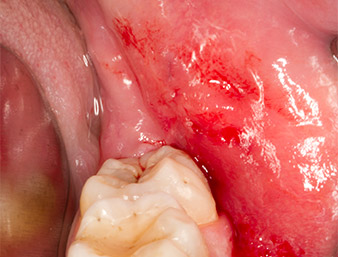

El tejido situado por encima del resto radicular no se había osificado por completo y constaba en su mayor parte de un tejido granulado con alteraciones inflamatorias (figura 4).

tejido granulado

Imagen 4: Dos ganchos de Langenbeck y un raspador según Prichard exponen el campo quirúrgico. Se distingue un tejido granulado de la primera osteotomía que no ha cicatrizado en su totalidad.